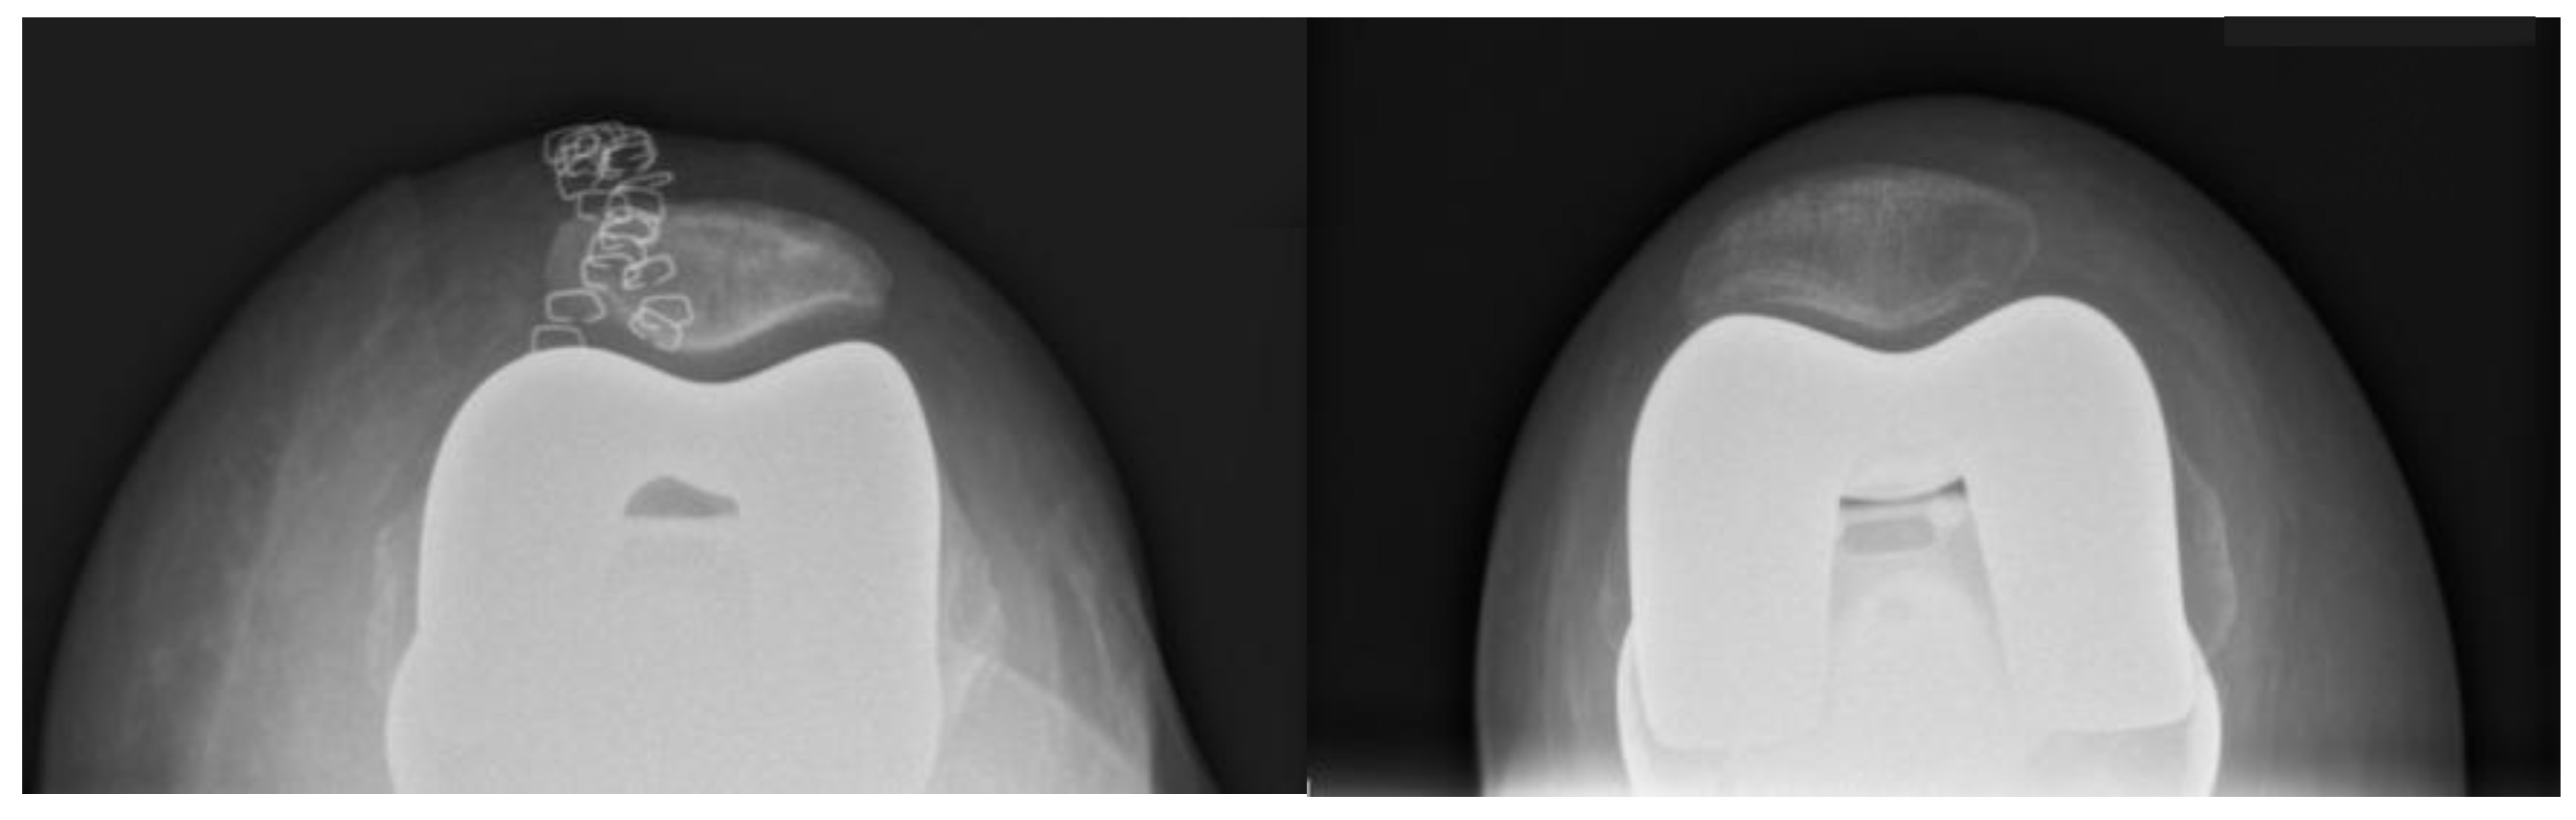

According to limitations previously highlighted [19], the planned intraoperative MPTA, LDFA, HKA, DFF, and TS angles of bone resections were extracted from the surgical report generated by the ROSA Knee System. Postoperative evaluation of radiographic outcomes was conducted three months postoperatively, and angle measurements were performed, as shown in Table 1. Standardized full-length weight-bearing anteroposterior lower limb radiographs and lateral 90° flexion knee and axial radiographs of the patella were obtained (Figure 1, Figure 2 and Figure 3). Incomplete radiographs because of a lack of weight bearing or incomplete extension warranted the exclusion from the present study. The arithmetic mean was calculated for each measurement performed by the two observers, and the obtained values were used for statistical purposes. Outliers from target angles were considered as follows: MPTA 90° ± 3°, LFDA 90° ± 3°, HKA 180° ± 3°, DFF 3° ± 3°, and TS 7° ± 3.

Figure 3. Example of an axial radiograph of the patella (Merchant view) used for measurements.